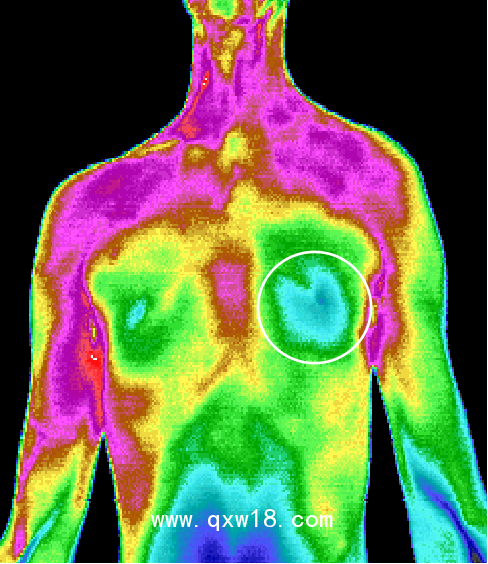

中醫(yī)熱CT是醫(yī)學(xué)技術(shù)和紅外攝像技術(shù)、計(jì)算機(jī)多媒體技術(shù)結(jié)合的產(chǎn)物,人體是一個(gè)天然的生物發(fā)熱體,由于解部結(jié)構(gòu)、組織代謝、血液循環(huán)及神經(jīng)狀態(tài)的不同,機(jī)體各部位溫度不同,形成不同的熱場,中醫(yī)熱CT被動接收人體組織細(xì)胞代謝熱源,可以反映出人體局部0.05°C~0.1°C的溫度微弱變化,0介入、0損傷、0輻射、0痛苦,結(jié)合Al智能分析可將傳統(tǒng)中醫(yī)通過“四診八綱”等原始手段獲取的人體信息,通過數(shù)值化和可視化的彩色圖像,形象客觀的呈現(xiàn)出來觀測臟腑的寒熱狀態(tài)、經(jīng)絡(luò)氣血流通情況、中醫(yī)藥效果的可視化觀察,針灸,推拿按摩,刮癡拔罐等治療的指導(dǎo)及效判定、參與九種體質(zhì)的評測,拓展了中醫(yī)四診,增加了中醫(yī)的“第五種診斷方法”,推動中醫(yī)現(xiàn)代化的發(fā)展,被形象的比喻成“扁鵲之眼”

???中醫(yī)熱CT檢測最重要的一個(gè)優(yōu)勢就是早期預(yù)警,X光、B超、CT等檢測技術(shù)都屬于結(jié)構(gòu)影像技術(shù),只有在疾病形成病灶之后才能發(fā)現(xiàn)疾病。而疾病在出現(xiàn)組織結(jié)構(gòu)和形態(tài)變化之前,細(xì)胞代謝就會發(fā)生異常。中醫(yī)熱CT可以反映出人體后部0.05°C~0.1C的溫度微弱變化,因此能更早地發(fā)現(xiàn)問題。檢測所得為高清晰度彩色圖像,具有更直觀、更形象的特點(diǎn),結(jié)合AI智能分析,所得結(jié)果精準(zhǔn)度更高,成為了目前我們認(rèn)知亞健康最有力的測評技術(shù)。

紅外熱CT檢測最重要的一個(gè)優(yōu)勢就是早期預(yù)警。X光、B超、CT等檢測技術(shù)它們都屬于結(jié)構(gòu)影像技術(shù),只有在疾病形成病灶之后才能發(fā)現(xiàn)疾病。而疾病在出現(xiàn)組織結(jié)構(gòu)和形態(tài)變化之前,細(xì)胞代謝就會發(fā)生異常。醫(yī)用紅外熱CT可以反映出人體局部0.05°C ~ 0.1°C的溫度微弱變化,因此能更早地發(fā)現(xiàn)問題。檢測所得為高清晰度彩色圖像,具有更 直觀、更形象的特點(diǎn),結(jié)合ai智能分析,所得結(jié)果精準(zhǔn)度更高,成為了目前我們認(rèn)知亞健康最有力的測評技術(shù)。紅外熱CT彌補(bǔ)了其他醫(yī)用影像設(shè)備的不足,并能很好地進(jìn)行影像互補(bǔ)。

ü?醫(yī)用級進(jìn)口設(shè)備:采用進(jìn)口醫(yī)用級紅外攝像頭,精準(zhǔn)捕捉人體0.05°—0.1°的溫度微弱變化,實(shí)時(shí)生成高清圖像。